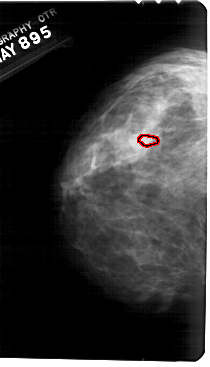

A_1685_1.LEFT_MLO

LEFT_MLO LINES 5476 PIXELS_PER_LINE 3301 BITS_PER_PIXEL 12 RESOLUTION 43.5 OVERLAY

FILE: A_1685_1.LEFT_MLO.OVERLAY

TOTAL_ABNORMALITIES 1

ABNORMALITY 1

LESION_TYPE CALCIFICATION TYPE PLEOMORPHIC DISTRIBUTION CLUSTERED

ASSESSMENT 4

SUBTLETY 1

PATHOLOGY BENIGN

TOTAL_OUTLINES 1

BOUNDARY